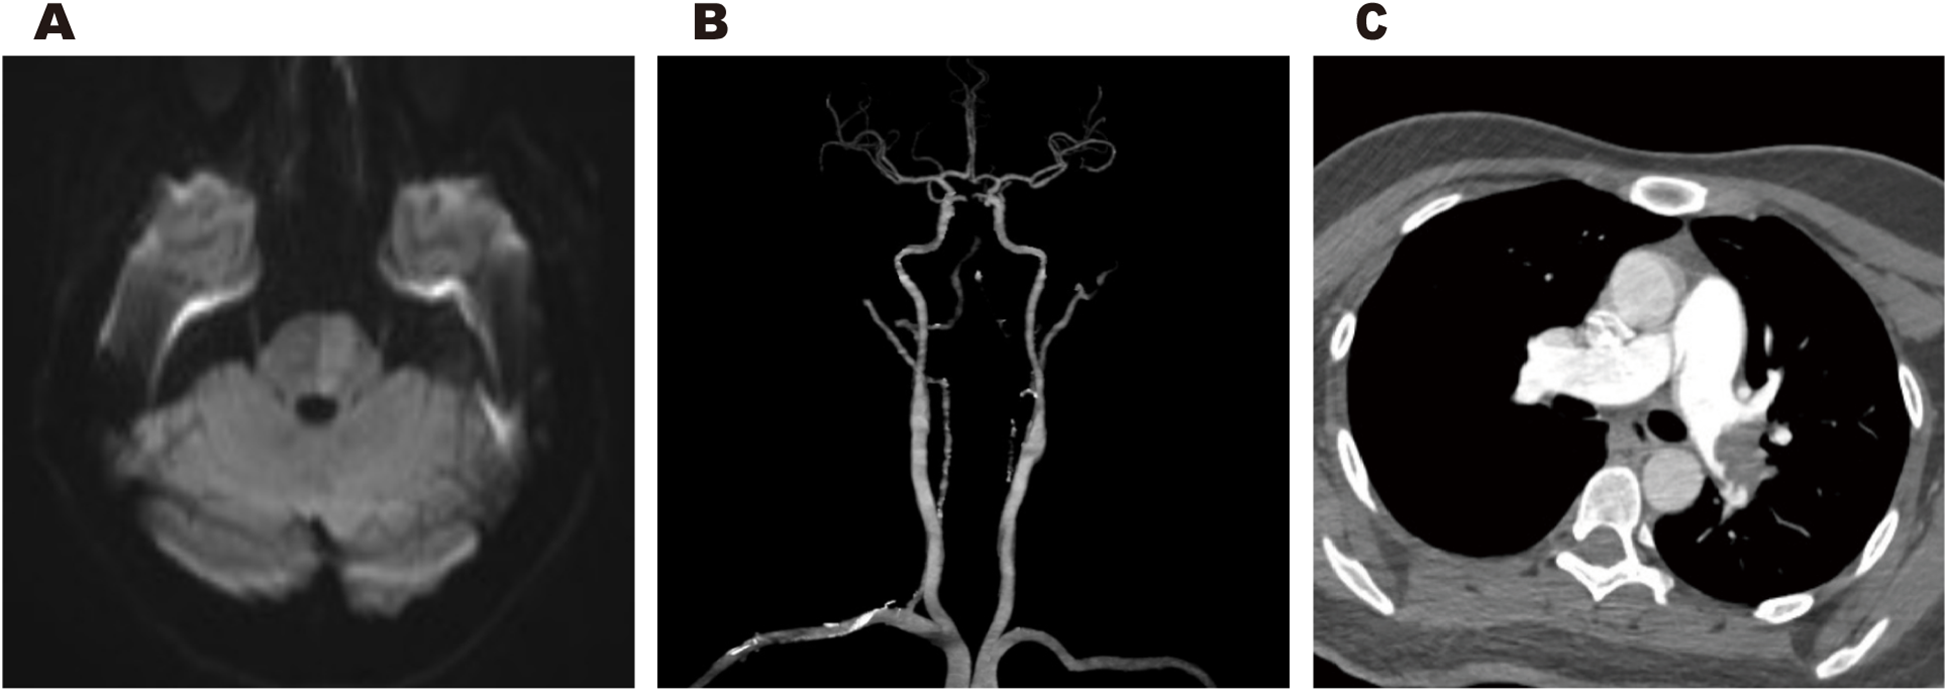

Cranial magnetic resonance imaging (MRI) revealed an acute pontine infarction (Figure 1A). Head and neck computed tomography angiography (CTA) showed basilar artery occlusion (Figure 1B) and incidentally detected left pulmonary artery embolism (Figure 1C), suggesting the possibility of multisystem embolism. Further digital subtraction angiography (DSA) of the whole brain confirmed interruption of blood flow in the distal basilar artery (Figure 2A). Pulmonary angiography revealed left pulmonary artery embolism (Figure 2B). Antegrade venography of the lower extremity deep veins showed bilateral iliac vein thrombosis (Figures 2C,D). The patient underwent emergency mechanical thrombectomy of the basilar artery and placement of an inferior vena cava filter (Figure 3B). Post-operatively, imaging evaluation showed the basilar artery was patent (Figure 3A), and the patient was transferred to the neurology department for further treatment.

Figure 1

Cranial MRI revealed an acute pontine infarction (A). Head and neck CTA revealed basilar artery occlusion (B), and incidentally showed left pulmonary artery embolism (C).